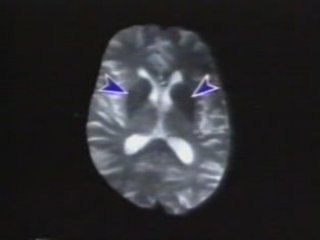

El hospital de pediatría del Centro Médico Nacional Siglo XXI del #IMSS realizó su primer trasplante de células madre en un niño que padecía cáncer.